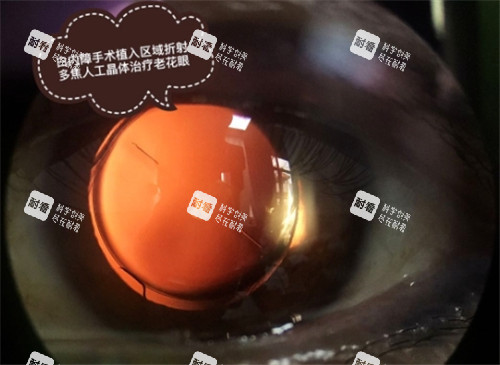

多样化的治疗方案:华厦眼科医院除了常见的超声乳化技术外,还提供飞秒激光辅助白内障手术。

飞秒激光能够更更好地制作切口和撕囊,提高手术的靠谱性和较准性。

对于一些对视力要求较高的患者,如飞行员、画家等,这种手术方式能更好地满足他们的需求。